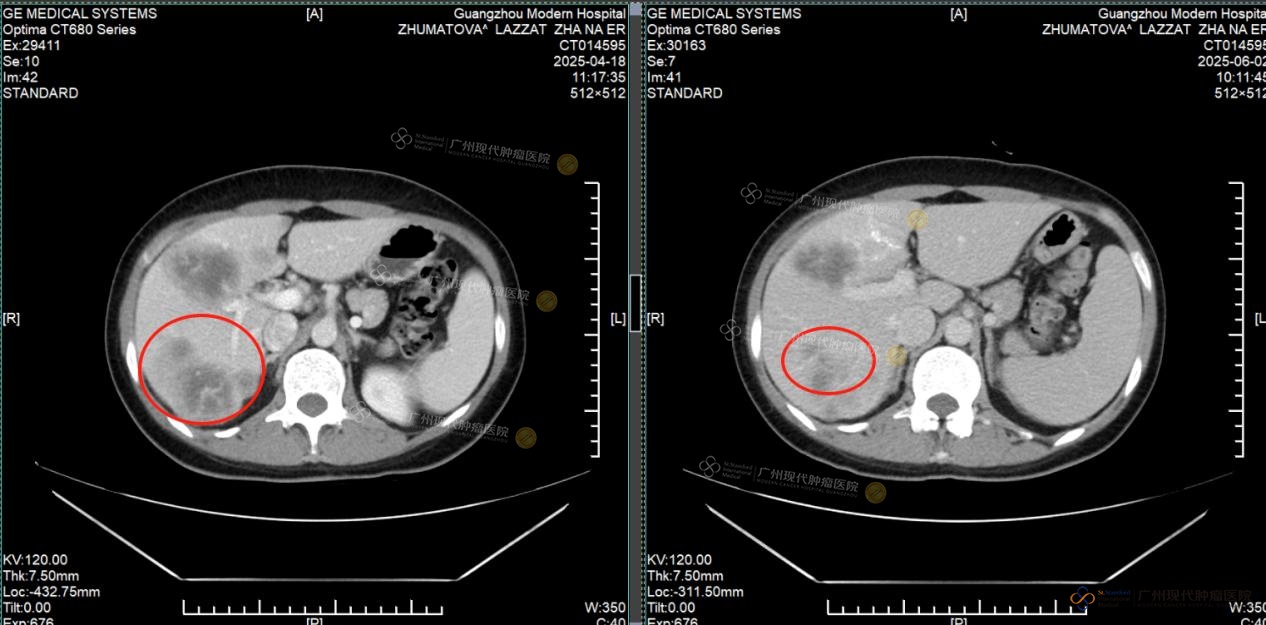

Lesi metastasis hati: sebelum pengobatan vs sesudah pengobatan, sebagian besar tumor sudah hilang

Pada April 2025, Lazzat datang ke rumah sakit kami ditemani oleh kakaknya dan menjalani pemeriksaan menyeluruh. Hasil CT menunjukkan bahwa terdapat massa tumor pada payudara kiri dengan ukuran sekitar 2×1cm, serta banyak lesi metastasis di hati, dengan diameter nodul terbesar lebih dari 4cm. Fungsi hati juga telah terpengaruh oleh tumor.

Setelah menjalani 2 siklus pengobatan, tumor payudara Lazzat berhasil dihilangkan sepenuhnya dan tidak terdeteksi lagi saat pemeriksaan ulang. Lesi metastasis di hati menyusut lebih dari setengah, fungsi hati kembali normal, dan penanda tumor seperti CEA dan CA153 menunjukkan penurunan yang signifikan. Berkat perawatan yang cermat dari tenaga medis, fungsi hatinya membaik, rasa lelah dan lemas pun berkurang secara nyata, dan ia kembali merasakan semangat hidup yang sudah lama hilang.